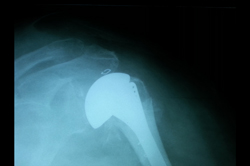

Shoulder Replacement